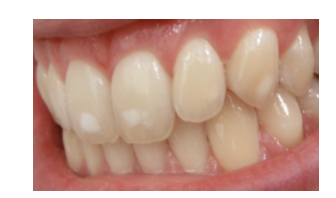

Enamel Hypocalcification

Abnormal Mineralization

* results in white spots